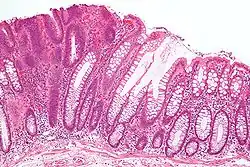

![]() | |

| Micrograph of a tubular adenoma (left of image), a type of colonic polyp and a precursor of colorectal cancer. Normal colorectal mucosa is seen on the right of the image. H&E stain. | |

Adenoma is a benign tumor of glandular tissue, such as the mucosa of stomach, small intestine, and colon, in which tumor cells form glands or gland-like structures. In hollow organs (digestive tract), the adenoma grows into the lumen - adenomatous polyp or polypoid adenoma. Adenomatous polyps may be classified based on morphology in order to identify lesions at increased risk of malignant transformation. For example, adenomatous polyps in the colon may be pedunculated (lobular head with a long slender stalk) or sessile (broad base).

The adenomatous proliferation is characterized by different degrees of cell dysplasia (atypia or loss of normal differentiation of epithelium) irregular cells with hyperchromatic nuclei, stratified or pseudostratified nuclei, nucleolus, decreased mucosecretion, and mitosis. The architecture may be tubular, villous, or tubulo-villous. Basement membrane and muscularis mucosae are intact.